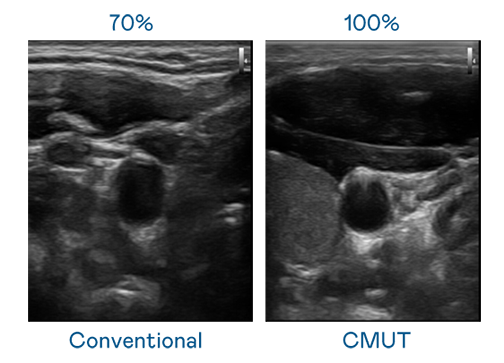

CMUT 技术是一种用电容式微机电元件来产生超音波讯号的技术。与传统 PZT 压电式技术相比,CMUT 频宽增加 30%,更宽频的超音波讯号让影像解析度大幅提升,是实现高影像品质医疗超音波扫描、促进精准医疗发展的关键技术。

大频宽带来超清晰影像

超音波影像的解析度高低,首先取决于探头能发出的讯号频宽。澳亚国际 CMUT 可提供高清晰的超音波讯号,提供高频宽、高灵敏度、影像纹理细节更高的超音波影像,协助医护人员缩短影像判读时间及利用精准的医疗影像进行诊断。